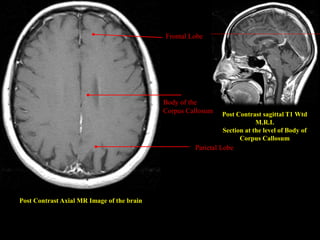

Post Contrast Axial MR Image of the brain

Post Contrast sagittal T1 Wtd

M.R.I.

Section at the level of Body of

Corpus Callosum

Parietal Lobe

Body of the

Frontal Lobe